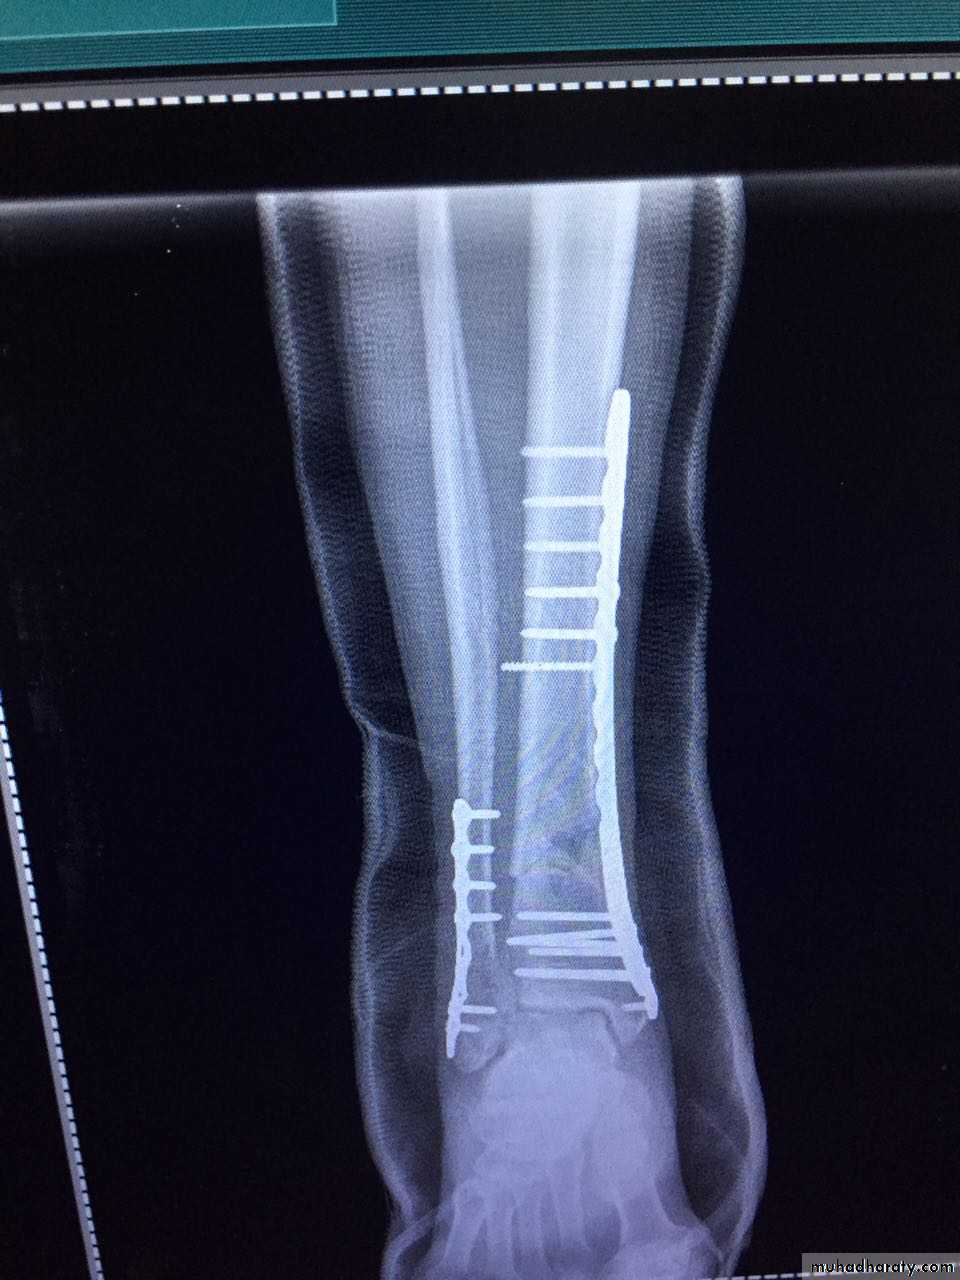

INTERNAL FIXATION

Indications

advantages